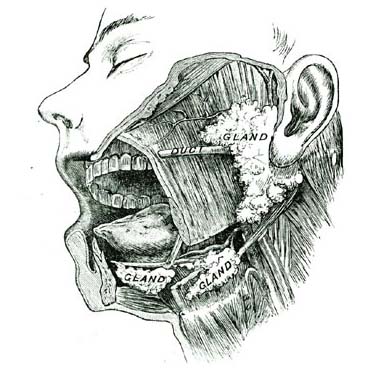

8. The Salivary (sal´-i-vary) Glands.—There are three pairs of salivary glands. They form a fluid called the saliva (sa-li´-va). It is this fluid which moistens the mouth at all times. When we eat or taste something which we like, the salivary glands make so much saliva that we some[Pg 31]times say the mouth waters. One pair of the salivary glands is at the back part of the lower jaw, in front of the ears. The other two pairs of glands are placed at the under side of the mouth. The saliva produced by the salivary glands is sent into the mouth through little tubes called ducts.

15. Lymphatic Glands.—Here and there, scattered through the body, are oval structures into each of which many lymphatic vessels are found to run, as shown in the illustration. These are called lymphatic glands.